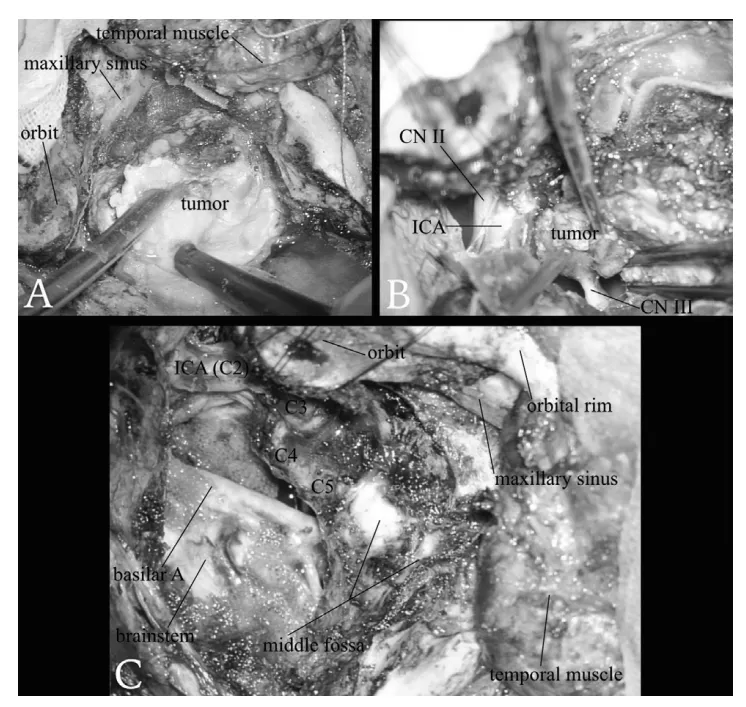

肿瘤与海绵窦段颈内动脉之间的轻度粘连,有助于实现肿瘤海绵窦内部分的完整切除(图2A–C)。

术中:(A)使用超声吸引器 切除肿瘤的右侧中颅窝部分。(B)右侧动眼神经 完全被肿瘤包绕、侵犯。(C)通过经颧骨-经海绵窦入路结合扩大中颅窝入路 实现肿瘤大体全切 后的最终术野。随着肿瘤海绵窦内部分的切除,右侧颈内动脉的海绵窦段 已被剥脱裸露。脑干的侧面得到了良好的显露。